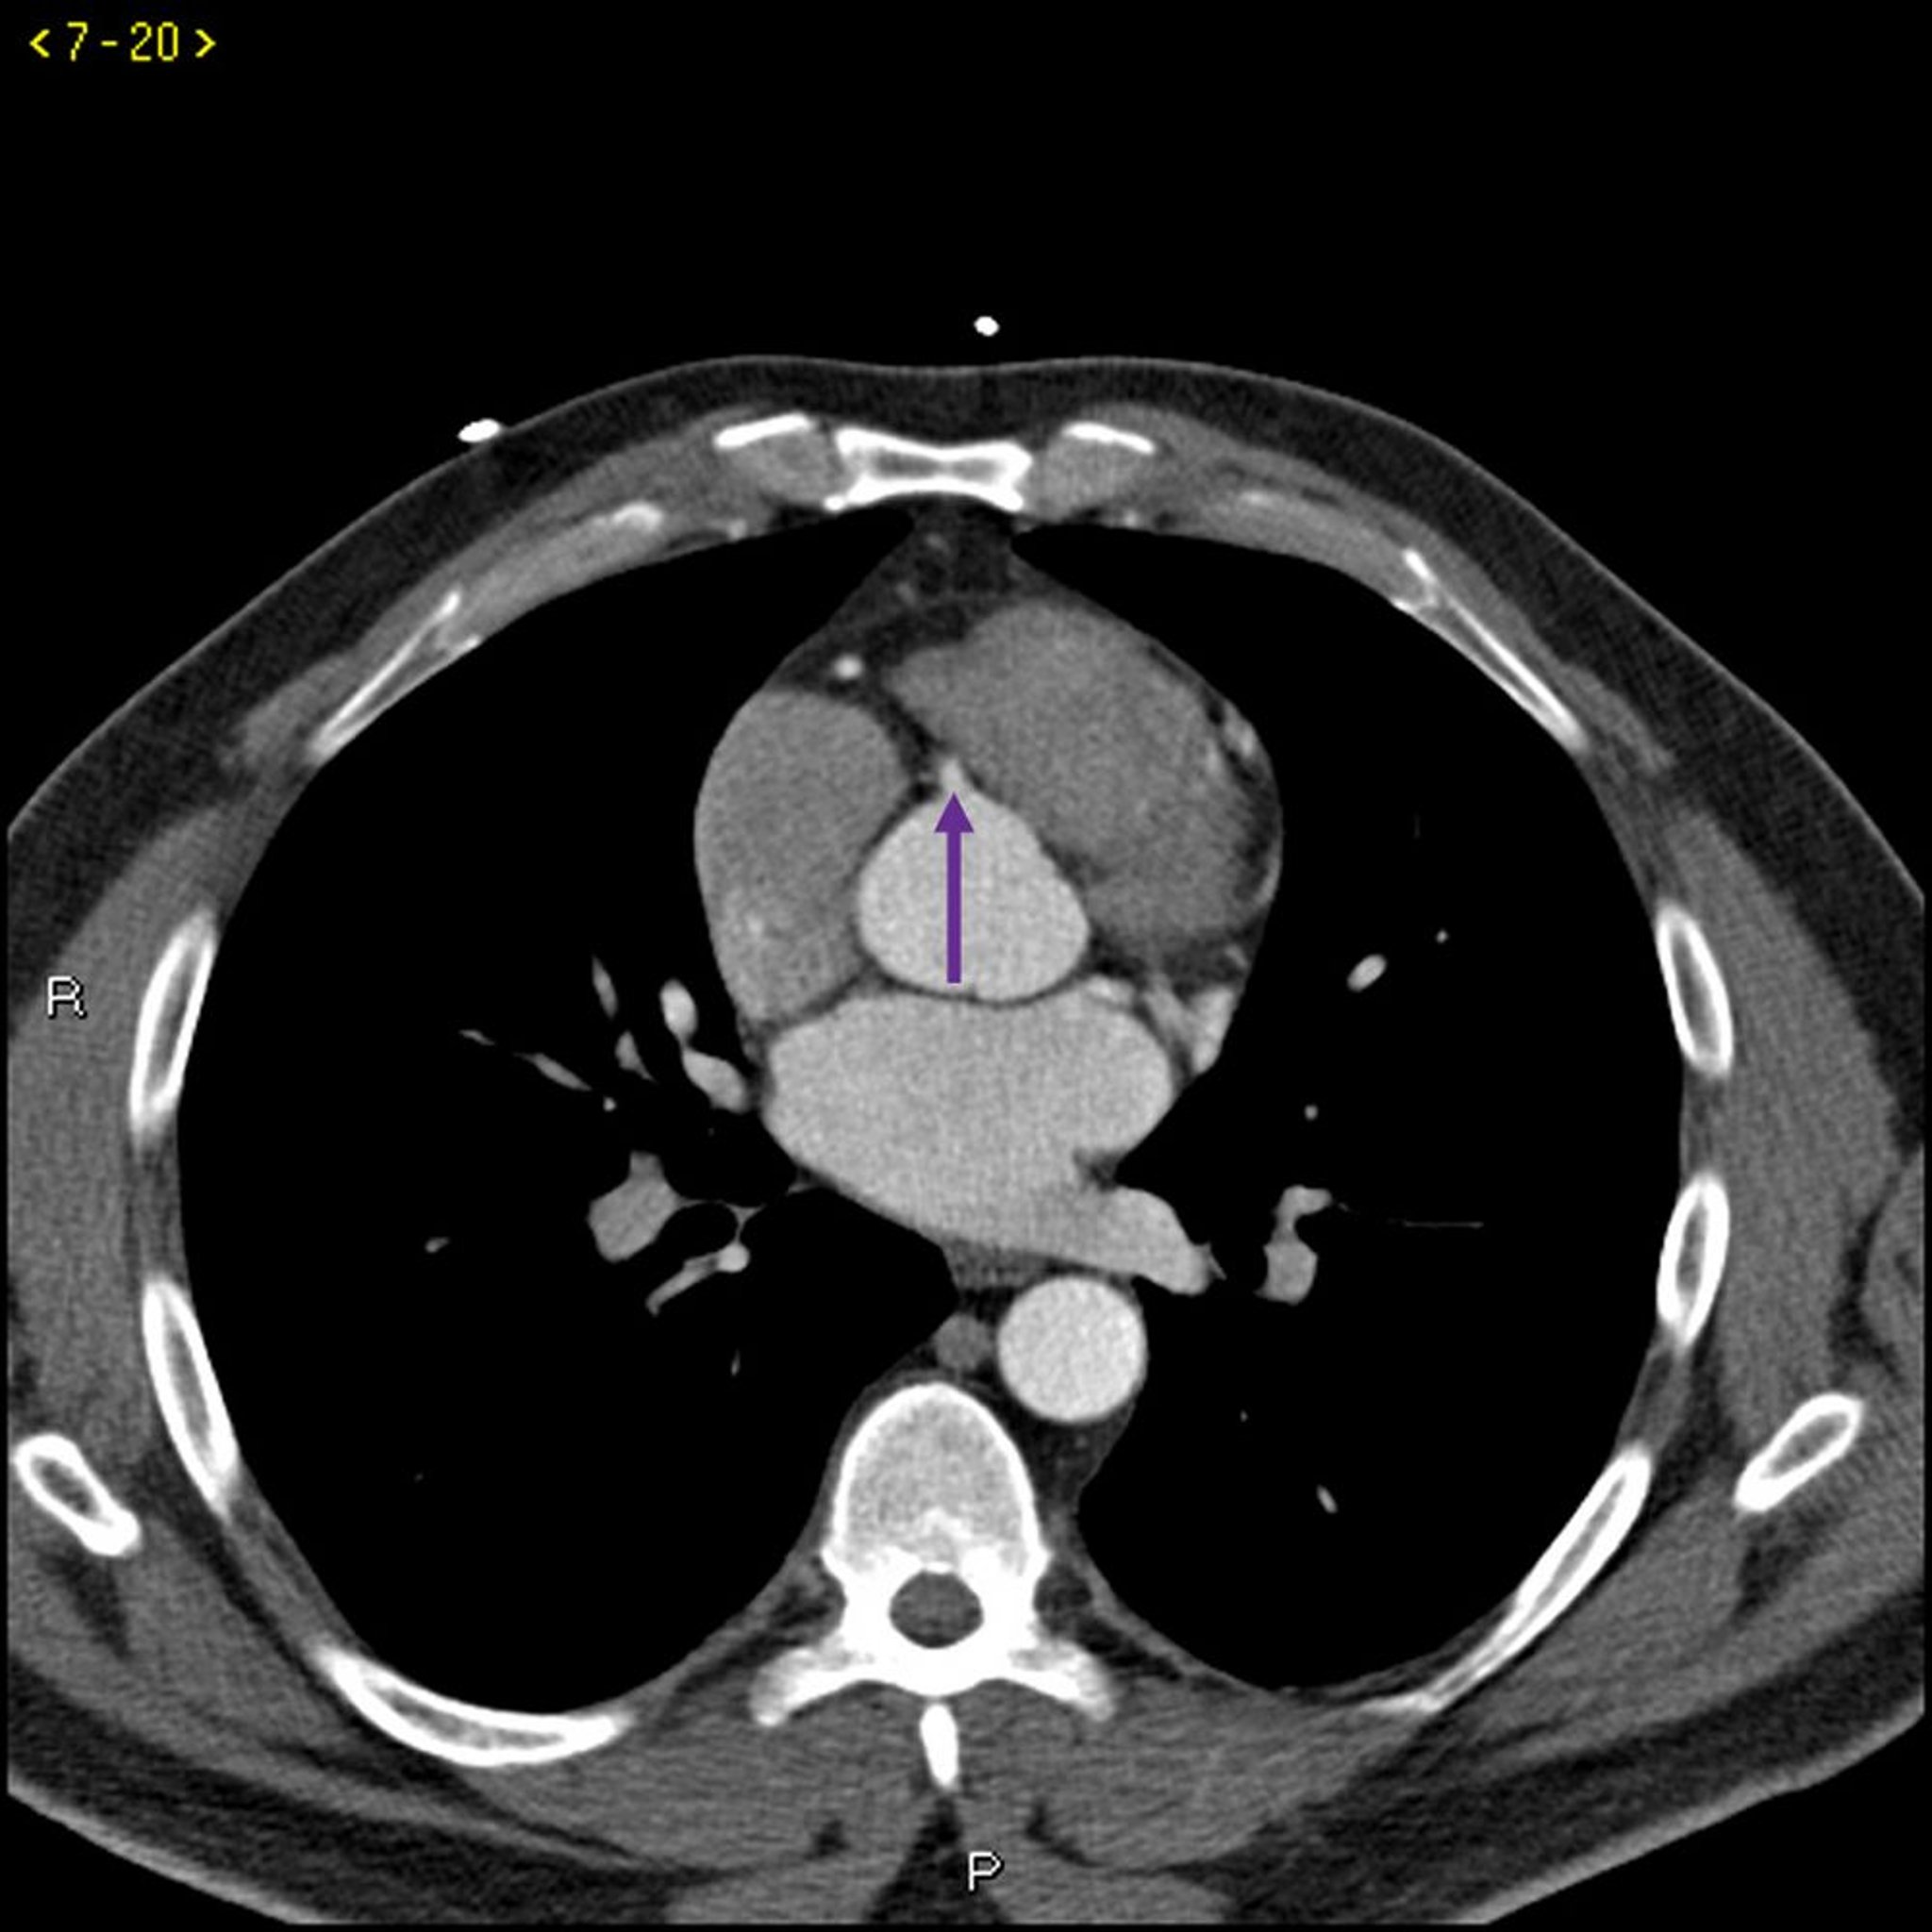

Contrast CT Showing Normal Coronary Arteries – Slide 5

This contrast CT shows normal coronary arteries. The left main is indicated by the red arrow. The left anterior descending and left circumflex arteries are indicated by the green and blue arrows respectively and the right coronary artery is indicated by the purple arrow.